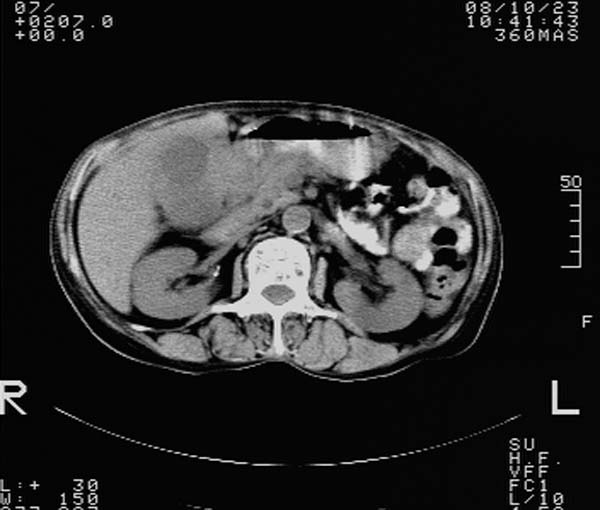

f,67y。反复右上腹痛。余无异常。

前五幅未服造影剂。后面图像有上传重复的。请战友们发表意见。

胆囊结石、胆囊癌伴邻近脏器受侵,不除外黄色肉芽肿性胆囊炎,建议增强扫描。肝多发囊性占位性病变,囊肿或囊性转移。

胆囊内结石,胆囊壁不规则增厚,胆囊胃窦区解剖结构欠清晰,楼主提示为少见病,考虑bouveret综合征?黄色肉芽肿性胆囊炎?肝内多发低密度占位,建议增强或b超

bouveret综合征(胆石性十二指肠幽门梗阻)应重点考虑。期待结果!